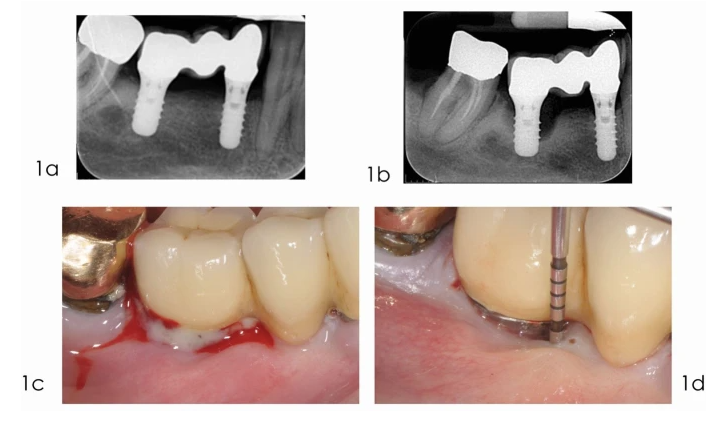

Sursa foto: nature.com

Indicații terapeutice în periimplantită pe baza criteriilor clinice

După evaluarea criteriilor clinice și radiologice, abordarea terapeutică în periimplantită trebuie să reflecte gradul de activitate al bolii și posibilitatea reală de control al infecției periimplantare. Parametri precum adâncimea pungii periimplantare, sângerarea la sondare, supurația și pierderea osoasă marginală oferă repere obiective pentru stabilirea nivelului de intervenție necesar.

Persistența pungilor periimplantare adânci, asociată cu sângerare la sondare sau supurație, indică necesitatea tratamentului chirurgical. În aceste situații, criteriile clinice sugerează că decontaminarea eficientă a suprafeței implantului nu poate fi obținută prin instrumentație limitată, iar accesul direct devine esențial pentru controlul procesului inflamator. Intervenția chirurgicală permite îndepărtarea completă a țesutului de granulație și evaluarea directă a configurației defectului osos.

Abordarea chirurgicală cu lambou de acces este indicată atunci când obiectivul principal este reducerea adâncimii pungilor periimplantare și stabilizarea parametrilor clinici. Această opțiune este susținută de criterii precum pierderea osoasă extinsă, defecte osoase cu configurație nefavorabilă pentru regenerare sau contexte locale în care modificările țesuturilor moi pot fi acceptate. Literatura arată că această abordare poate conduce la îmbunătățiri semnificative ale parametrilor clinici, însă menținerea rezultatelor depinde de controlul plăcii și de includerea pacientului într-un program riguros de întreținere periimplantară.

Abordarea reconstructivă este indicată în cazurile în care criteriile clinice și de sit sugerează un potențial favorabil pentru regenerare. Printre aceste criterii se regăsesc controlul eficient al plăcii bacteriene și al sângerării la nivelul întregii cavități orale, complianța pacientului față de un program de întreținere, absența factorilor de risc majori și prezența unui defect intraosos cu o configurație favorabilă. În aceste situații, tratamentul urmărește refacerea suportului osos periimplantar și stabilizarea țesuturilor moi, cu impact asupra prognosticului biologic și estetic.